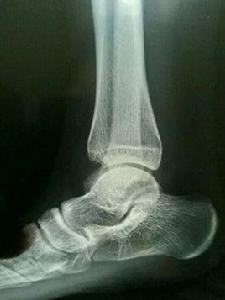

右距骨撕脫性骨折另外一種直白的解釋:韌帶(俗稱筋)跟肌肉和骨骼緊密相連,劇烈運動時韌帶極度收縮,導致韌帶控制相連的肌肉(再內層是肌腱)一塊極度收縮,收縮的幅度過大,同時骨骼突起和粗隆部分不夠結實,被肌腱的收縮力度一塊拉扯下來,從而造成撕脫性的骨折。

人在劇烈活動中可造成肌肉的收縮,與肌腱相連的骨的突起和粗隆部的一部分或者全部的骨質分離。由於韌帶牽拉造成韌帶附著處骨質隨韌帶一起剝離下來,形成碎骨片,稱為撕脫性骨折。(通俗點說就是肌肉肌腱拉力過大,在外力的作用下,導致附著的骨頭髮生骨折,撕裂下整塊或者一小部分的骨質殘片)

撕脫性骨折撕脫性骨折的症狀與骨折相近,以傷處疼痛及關節活動部分受限為主要表現,其次就是局部的腫脹,壓痛。脛骨髁間隆起撕脫性骨折是一種特殊類型的23關節內骨折,往往是前交叉韌帶或後交叉韌帶在脛骨附著部的撕脫性骨折。不適當的治療會導致畸形癒合,引起膝關節功能不穩。脛骨髁間隆起撕脫性骨折並移位多沿用傳統切開復位鋼絲內固定術治療。切開復位鋼絲內固定雖可有效的復位與固定骨折塊,但其有切口長,創傷大,術後功能鍛鍊極為痛苦和漫長,易發生膝關節僵直,加之髁間窩狹小操作不便等缺點。